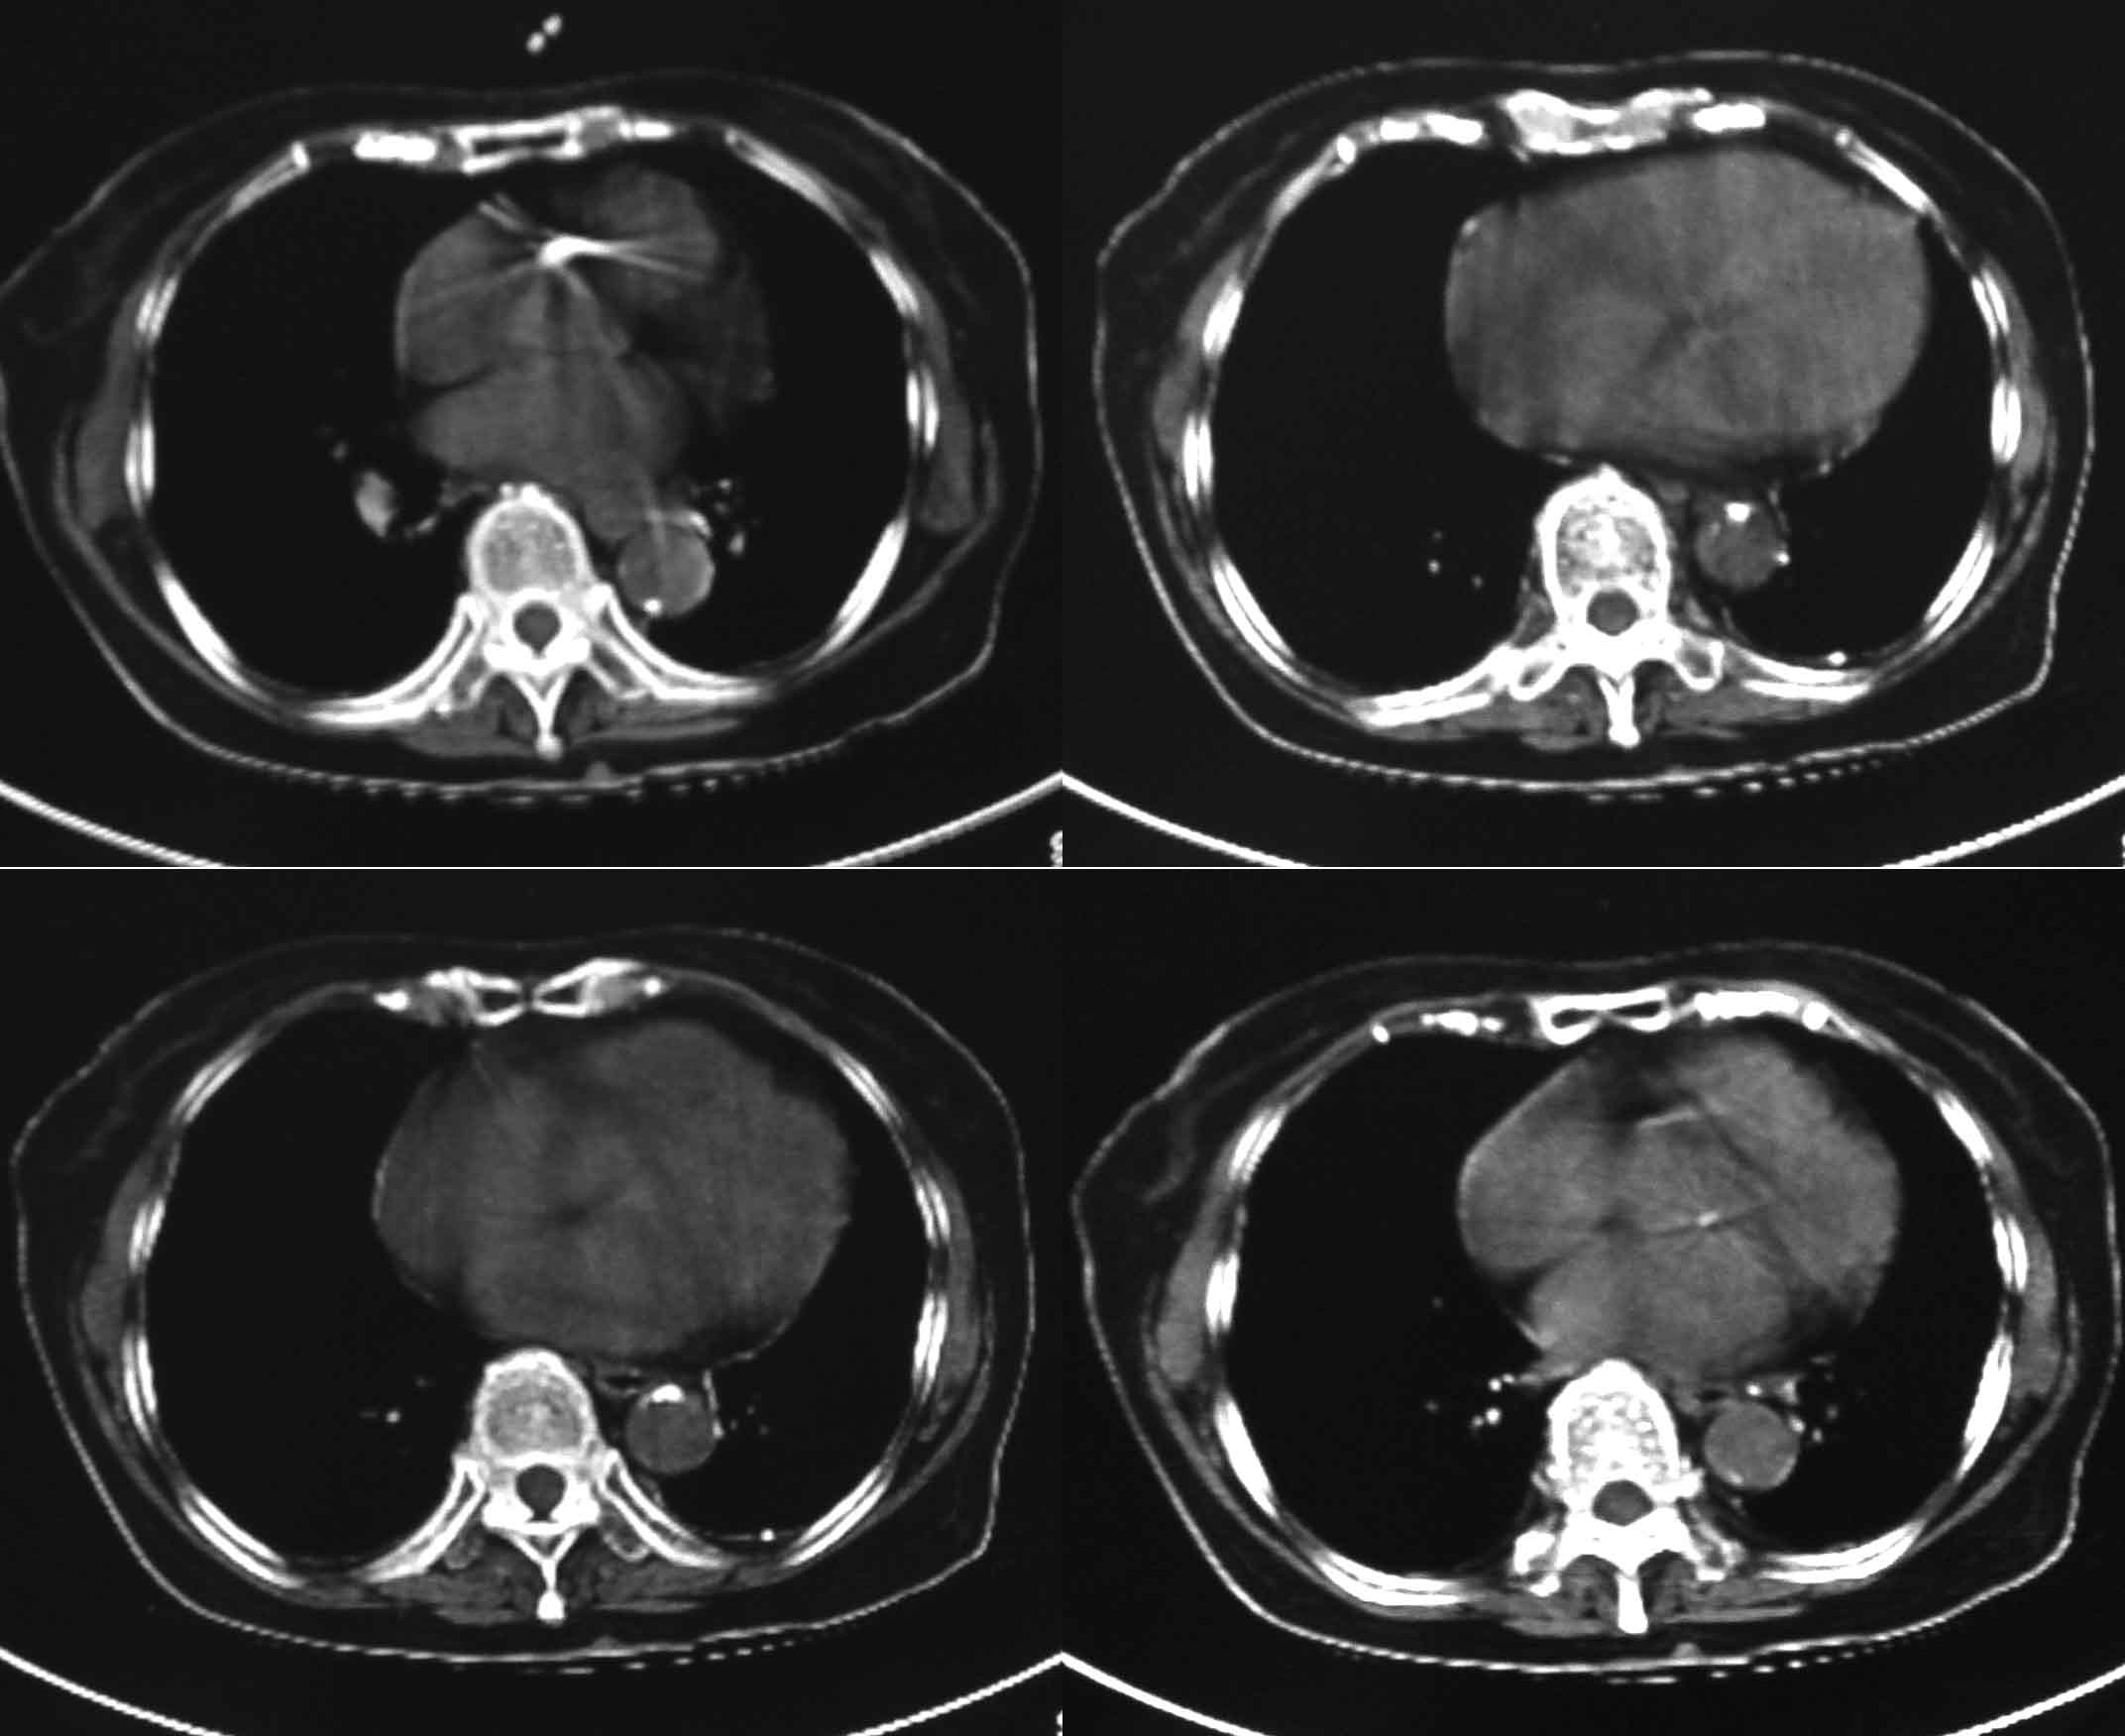

女69岁。时有咳漱、咳白色痰请老师们看看箭头所指是什么?ct值约-36.报告应该怎样写?谢谢!

考虑左后下胸内侧壁与胸膜之间脂肪影。

左后下胸内侧壁与胸膜之间脂肪影。

局限性胸膜肥厚,心影增大,建议心超检查

考虑左后下胸内侧壁与胸膜之间脂肪影。支持